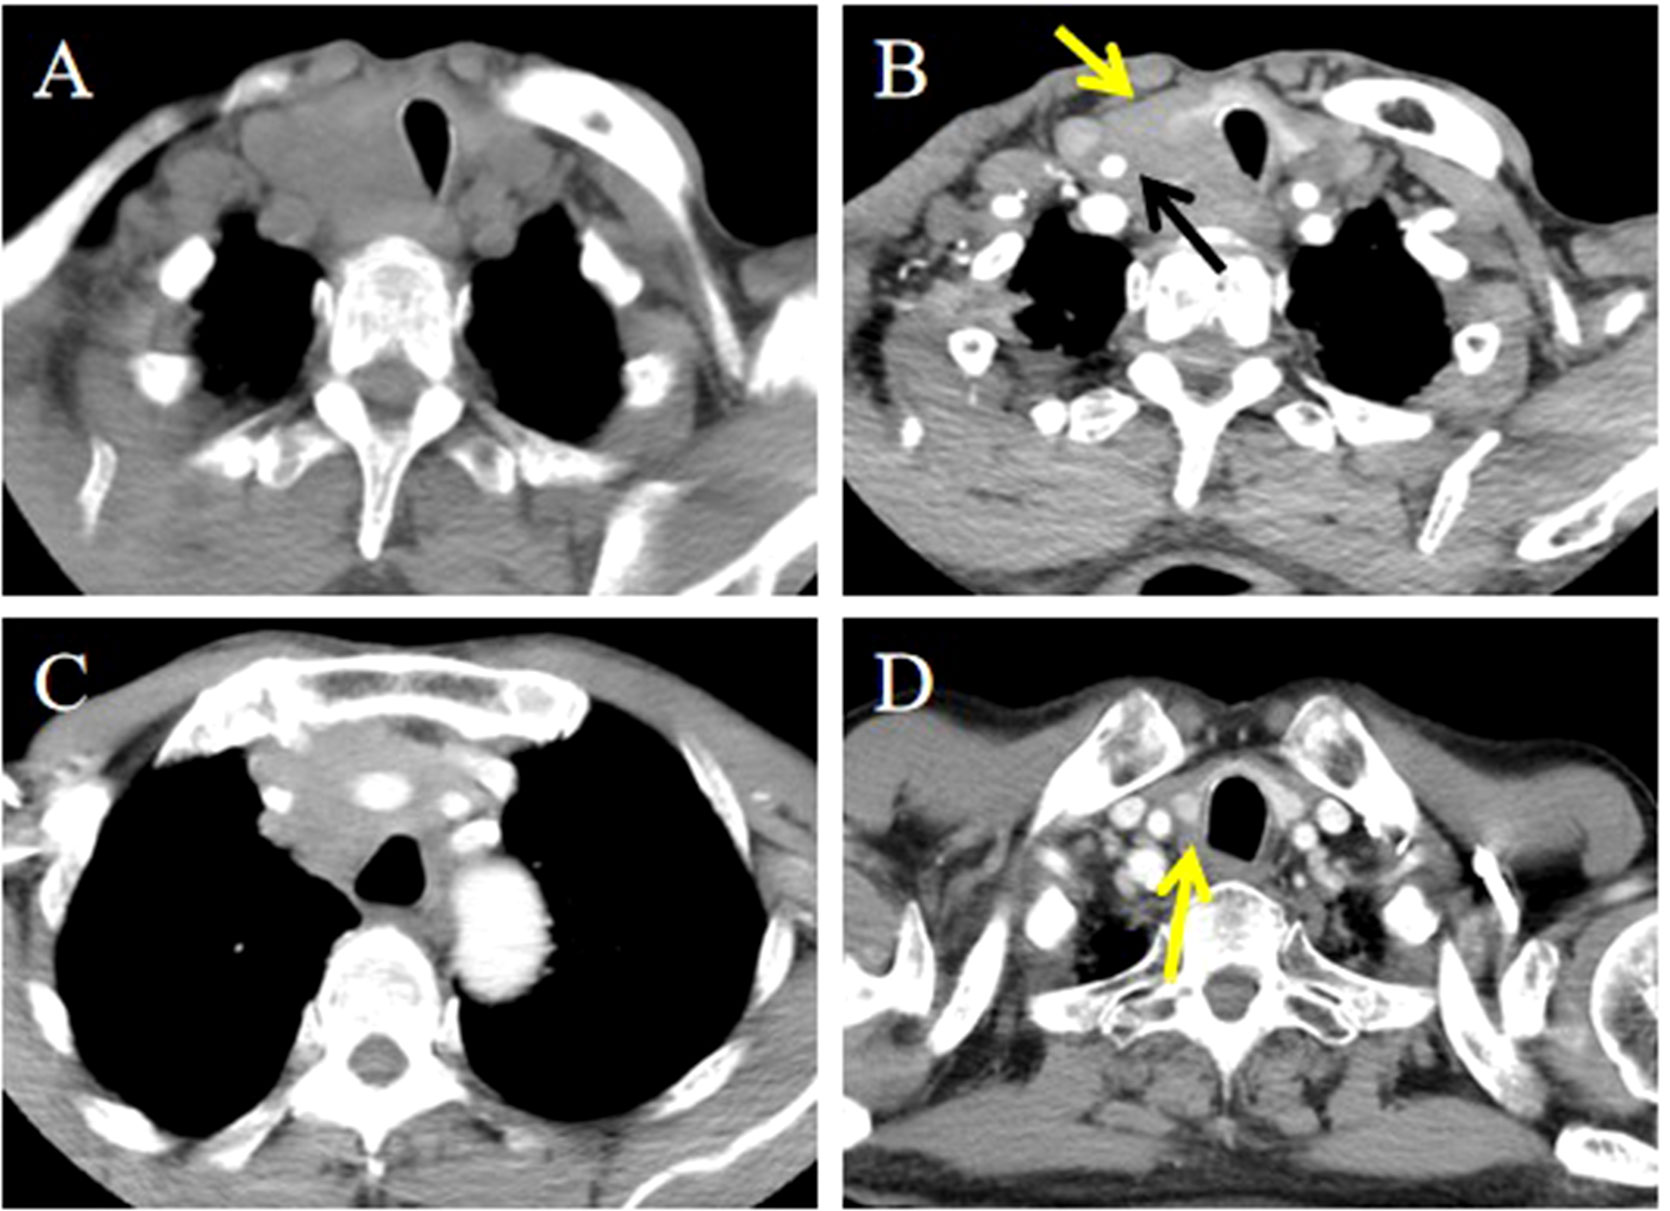

Objective: To summarize the clinical characteristics and imaging features of intrathyroid thymic carcinoma (ITTC), along with diagnostic and therapeutic approaches, to increase awareness of this rare disease. Methods: We retrospectively analyzed 14 patients with ITTC confirmed by core needle biopsy (CNB) and surgery combined with immunohistochemistry. The clinical and imaging findings, treatment, pathological findings and follow-up data of these patients were reviewed. Results: Thirteen patients were newly diagnosed and one relapsed at the original surgical site. All tumors were solitary, mostly located in the lower neck or upper chest, often in the tracheoesophageal groove with or without extension to the thyroid’s lower pole, and approximately two-thirds of patients presented with hoarseness. On CT, most lesions appeared as irregular, low-density soft-tissue masses, with calcification in two cases; contrast-enhanced CT revealed mild heterogeneous or homogeneous enhancement, and over half exhibited an arc-shaped interface with adjacent thyroid tissue. Most tumors were locally advanced, invading muscles, the supraclavicular fossa, tracheoesophageal groove, esophagus, tracheal wall, or mediastinal vessels. The diagnostic accuracy of fine-needle aspiration biopsy (FNAB) was low, whereas core needle biopsy (CNB) combined with immunohistochemistry was reliable. Ten patients underwent radical surgery, of whom three received adjuvant chemoradiotherapy and four adjuvant radiotherapy; four patients received radical chemoradiotherapy, and one received combined therapy including anlotinib, a novel tyrosine kinase inhibitor. The median follow-up was 86 months (range, 25–146), and three surgically treated patients developed local recurrence or pulmonary metastasis. Conclusion: CNB combined with immunohistochemistry is recommended when the characteristic and imaging manifestations suggest a diagnosis of ITTC. Especially for locally advanced cases, imaging-based diagnosis can be useful for analysis and to guide treatment.